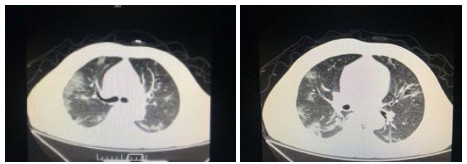

| 图 2 患者,女性,64岁,武汉籍,发病前1 d由武汉自驾车入沪,出现发热,体温39.9℃, 伴全身乏力,无咳嗽症状,无鼻塞,流涕症状,血白细胞总数及淋巴计数正常,甲乙型流感病毒筛查阴性,新型冠状病毒核酸检测阳性,肺部CT双肺多发磨玻璃结节,部分贴近胸膜,左肺有少量胸腔积液,局部小叶间隔增厚, 可见纤维条索影 Fig 2 Case 2, female, 64 years old, born in Wuhan. One day before the onset of the disease, she drove into Shanghai from Wuhan and had fever. Her body temperature was 39.9℃, with general asthenia, no cough, no nasal obstruction and running nose, normal WBC and lymphoid count, negative influenza A and B virus screening, positive novel coronavirus nucleic acid test. Lung CT showed multiple ground glass nodules, some of which were close to pleura, a small amount of pleural effusion in the left lung, and local interlobular septa was thickened, with visible fibrous streak shadow |

| 图 3 患者,女性,49岁,沪籍,发热10 d,体温最高38.5℃,伴乏力,肌肉酸痛,既往体健。否认武汉流行病学接触史,有菜场买菜史。血白细胞总数及淋巴计数正常,甲型、乙型流感筛查阴性,新型冠状病毒核酸检测阳性。肺部CT提示双肺磨玻璃结节,可见血管充血,增粗,穿行,部分贴近胸膜,伴小叶间隔增厚 Fig 3 Case 3, female, 49 years old, born in Shanghai, had fever for 10 days, body temperature 38.5℃, with fatigue, muscle pain, previous physical fitness. She denied the history of epidemic exposure of Wuhan, but had the history of shopping in market. Normal WBC and lymphoid count, negative influenza A and B virus screening, positive novel coronavirus nucleic acid test. Lung CT showed bilateral ground glass nodules with hyperemia, thickening and passage of blood vessels. Some were close to pleura with thickening of interlobular septum |